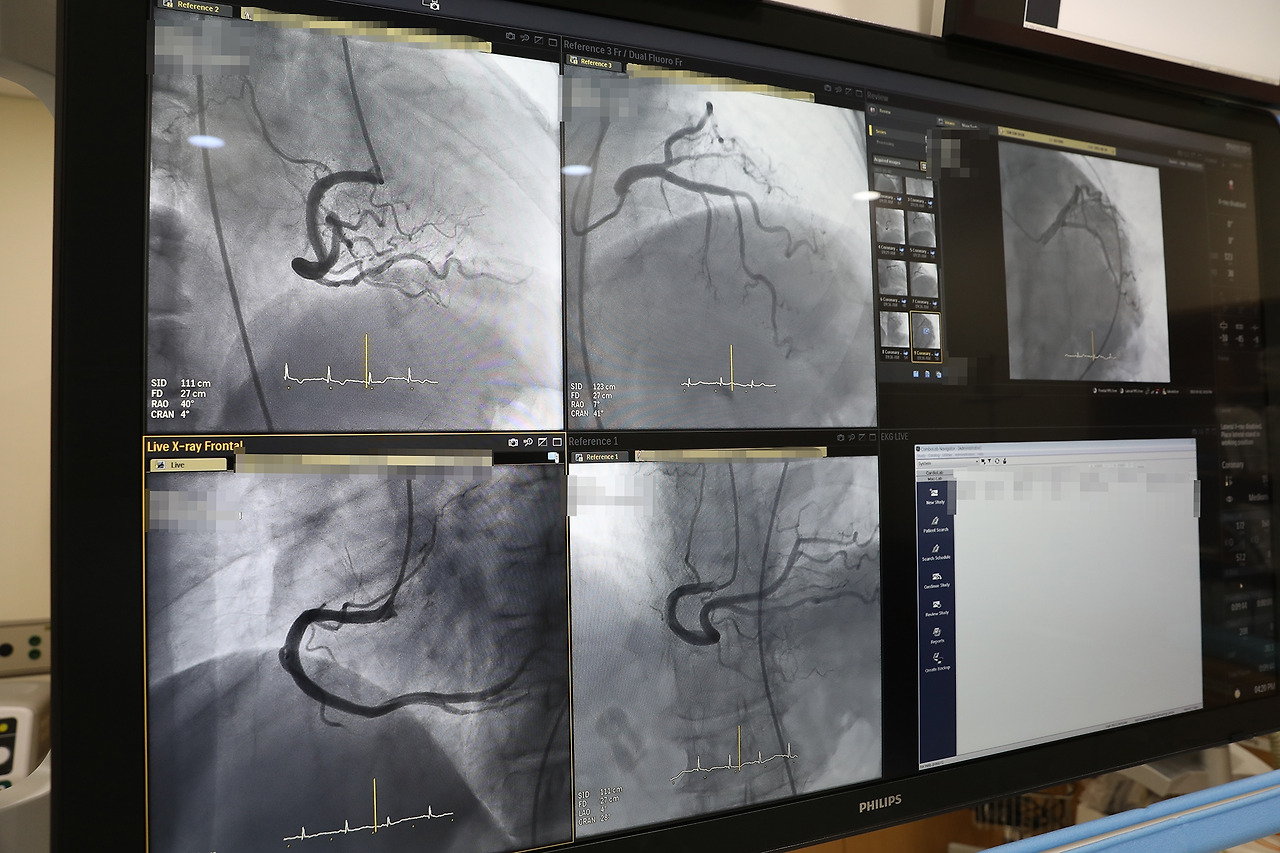

인제대학교 일산백병원(원장 이성순)이 초정밀 심장혈관조영 촬영 장비인 ‘아주리온(Philips Azurion 7B1212)’을 도입하고 3월 2일부터 본격적인 운영에 들어갔다.

‘아주리온’은 심혈관 중재시술을 시행할 때 사용하는 심혈관 조영촬영 장비다. 심근경색이나 협심증, 부정맥 등 심장혈관 질환을 진단하고 치료할 수 있다. 피부에 2~3mm 구멍을 뚫고 혈관에 조영제를 주입, 영상을 보면서 막힌 혈관을 찾아 치료하는 방식이다.

이번에 도입한 아주리온은 기존 장비에 비해 최대 80%가량 방사선 피폭량을 줄일 수 있다. 한 번의 조영제 사용으로 관상동맥뿐만 아니라 대동맥과 판막, 말초동맥 등을 포함한 광범위한 부위의 심장혈관도 한 번에 촬영할 수 있어 조영제 사용도 줄어든다. 또 혈관을 볼 수 있는 20인치 대형 화면(디텍터)이 장착돼, 한 화면에 넓은 부위의 심장혈관을 확인할 수 있다.

[사진] 인제대학교 일산백병원이 심근경색, 협심증, 부정맥 등을 진단하고 치료하는 혈관조영 촬영 장비인 ‘아주리온(Philips Azurion 7B1212)’을 도입하고 본격적인 운영에 들어갔다..jpg

의료진 시술 편의성도 높아졌다. 스텐트 삽입 전·후 상태도 체크할 수 있고, 움직이는 혈관과 그 위에 다시 현재 혈관 영상을 보여주는 오버레이 영상 등도 볼 수 있다.

이밖에 ▲아주리온(심혈관 조영기) 장비와 응용 프로그램을 제어할 수 있는 터치스크린(Touch Screen Module Pro) ▲시술 중 실시간 영상 화면을 조정하거나 레퍼런스 정보를 적용·설정하는 플렉스비전 프로(FlexVision Pro) ▲시술 준비 절차를 맞춤형으로 설정하는 프로시저카드(ProcedureCards) ▲조정실 여러 컴퓨터와 하드웨어를 단 두 개 모니터에서 통합적으로 관리하는 플렉스스팟(FlexSpot) 등이 장착돼 있어, 시술시간은 줄어들고 의료진의 효율적인 진단과 치료에 도움을 준다.